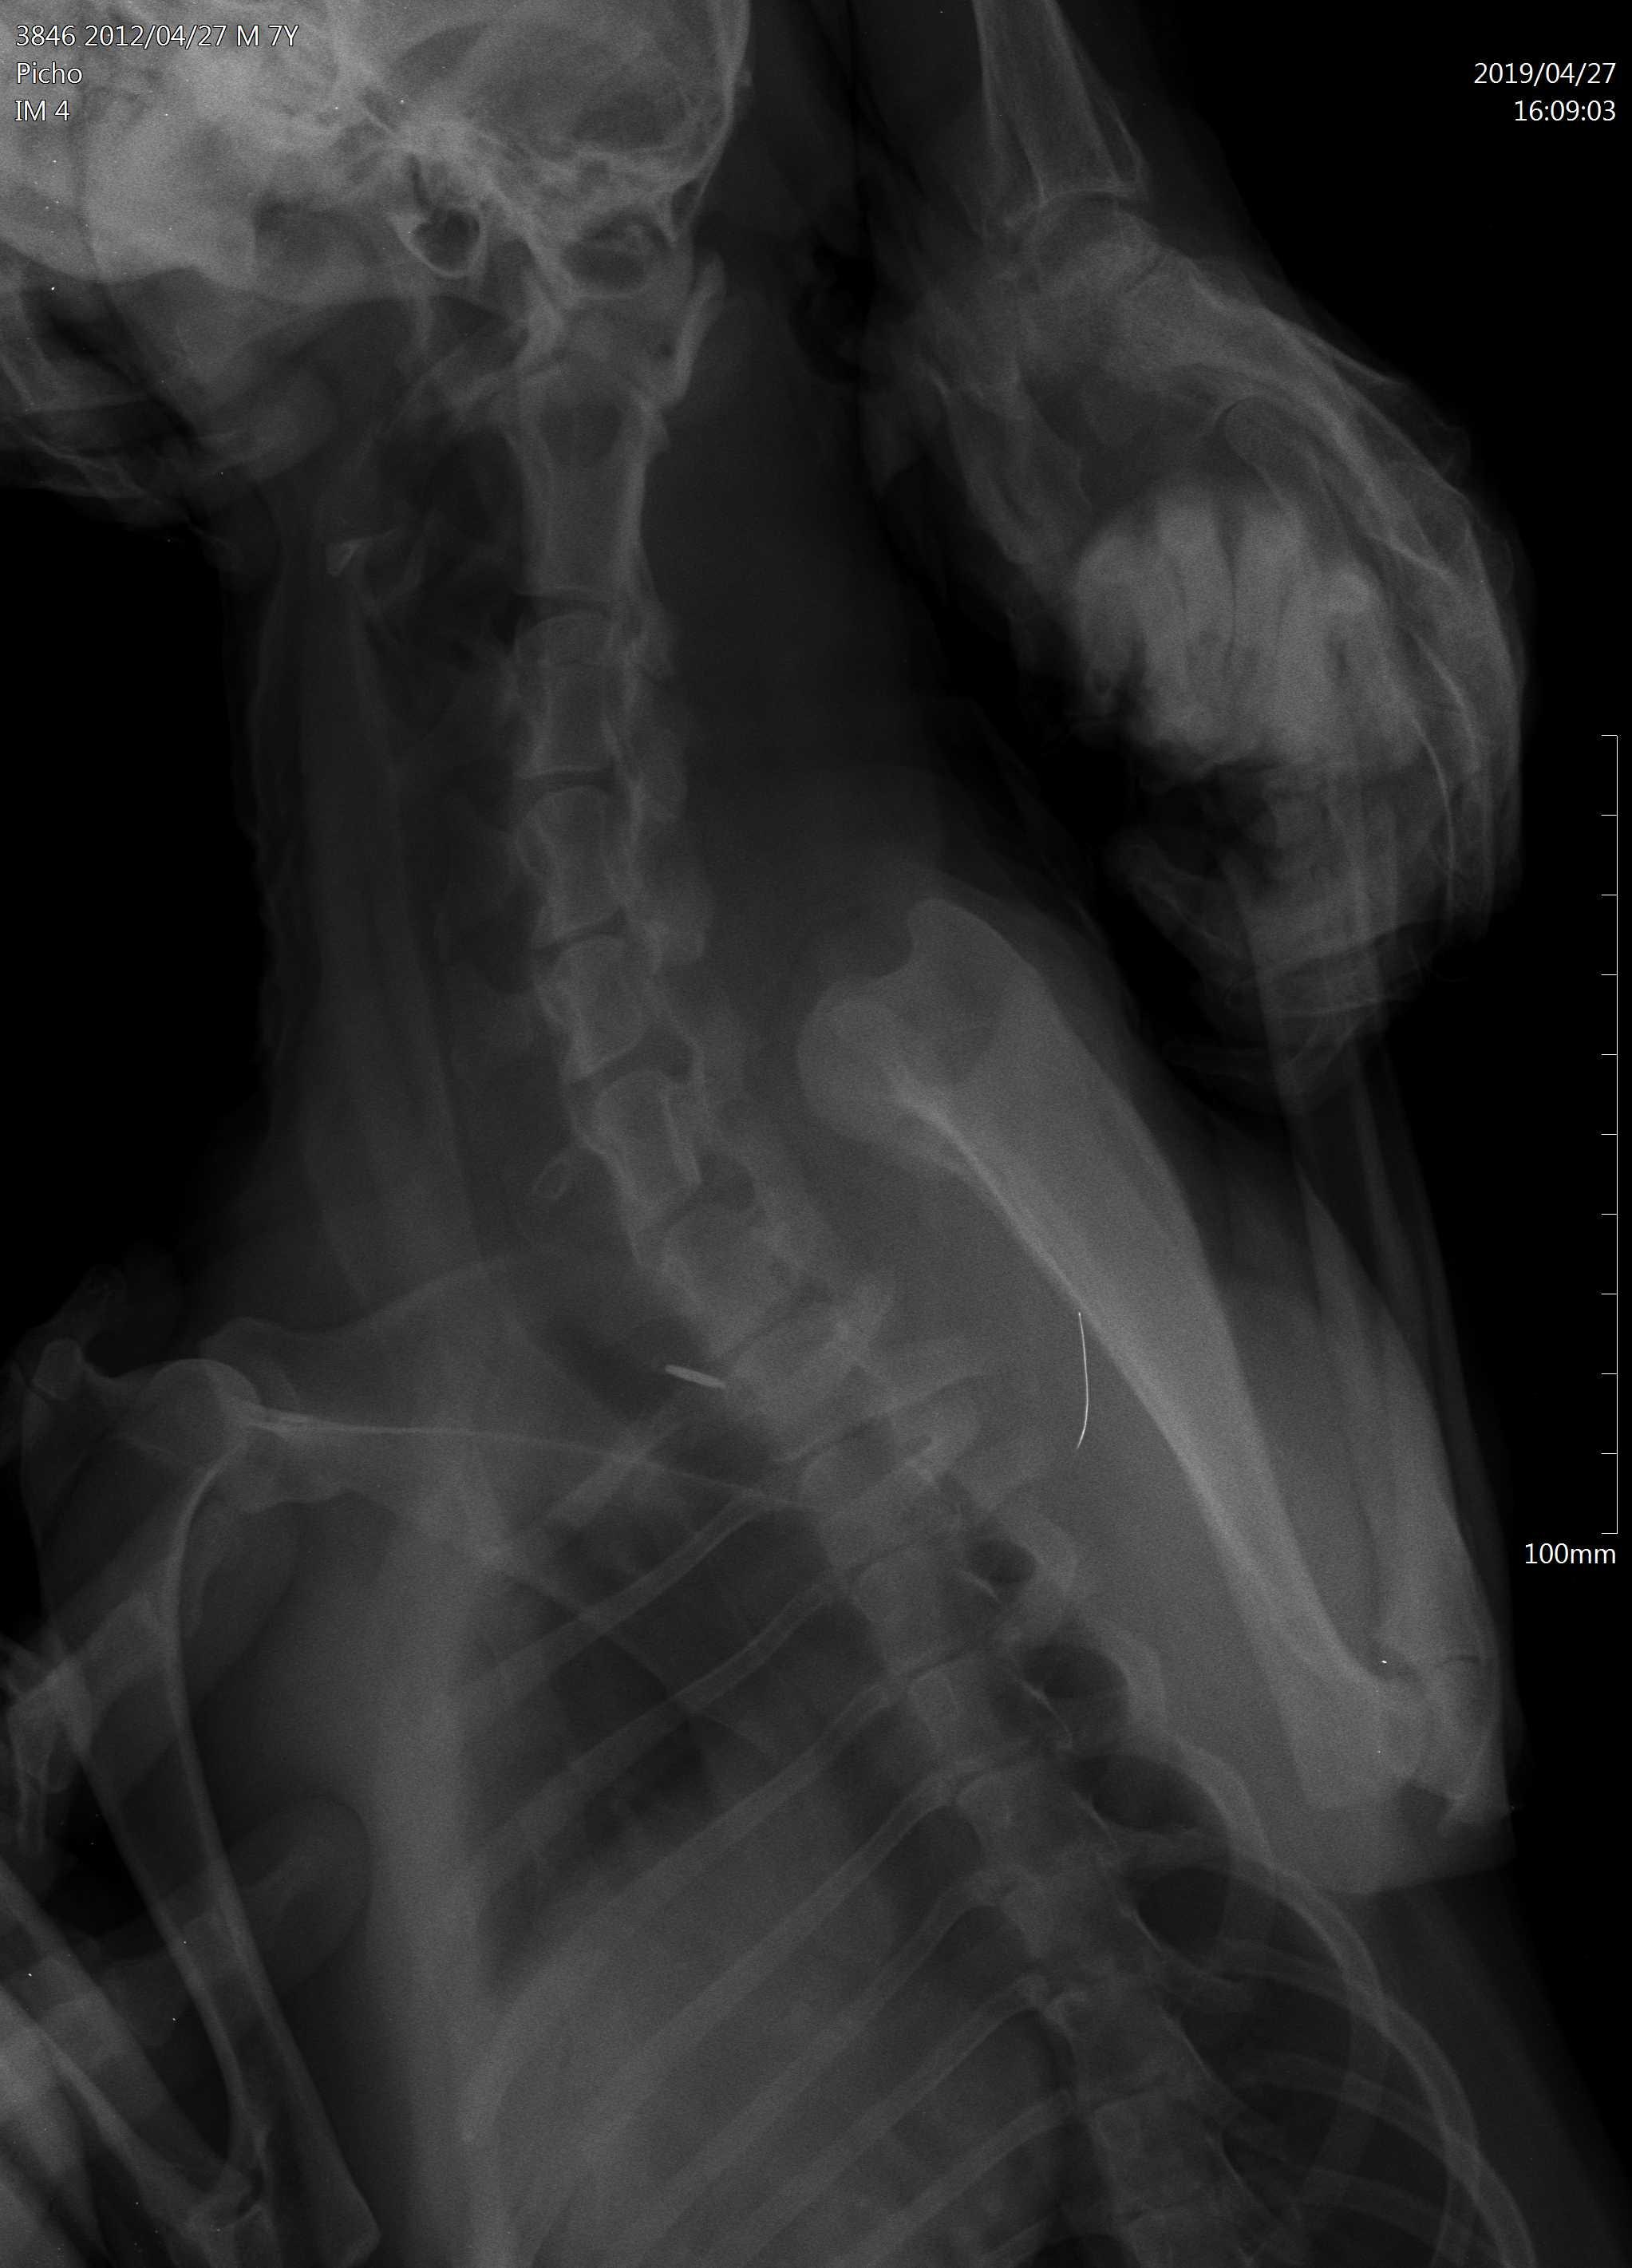

Dears, My dog had a seizure 1 month ago, 2 days ago he was vomiting. Then he was playing with my daughter and she accidentally hit him somewhere in the neck as she says, in the morning we found him paralysed with all legs he can't walk. We had an X-ray, attached see pics, our vet says he has a fluid between neck and spine that causes brain compression and he needs surgery. Please advise, my daughter is nervous she thinks that it is because of her, could this be the reason?

I hardly think your daughter could have hit Pich hard enough to cause this. It is more likely that this condition was underlying already especially with the history of a seizure. The x-rays are difficult to assess on this forum - when we try to enlarge them they get very grainy so I cannot comment on that part. Hope this helps. Best wishes.

I remember this question from before. There is no way your daughter hit this dog hard enough to cause paralysis unless she ran him over in a car or hit him with a baseball bat. Regardless, of whether she did or didn't cause it Pich needs surgery. I see the fluid your vet has noted. Your only options are to do the surgery or humane euthanasia - you cannot let him suffer like this. This has already been going on for weeks. Please do the surgery or relieve his suffering. I'm sorry you are going through this but you need to do what is best for Pich.